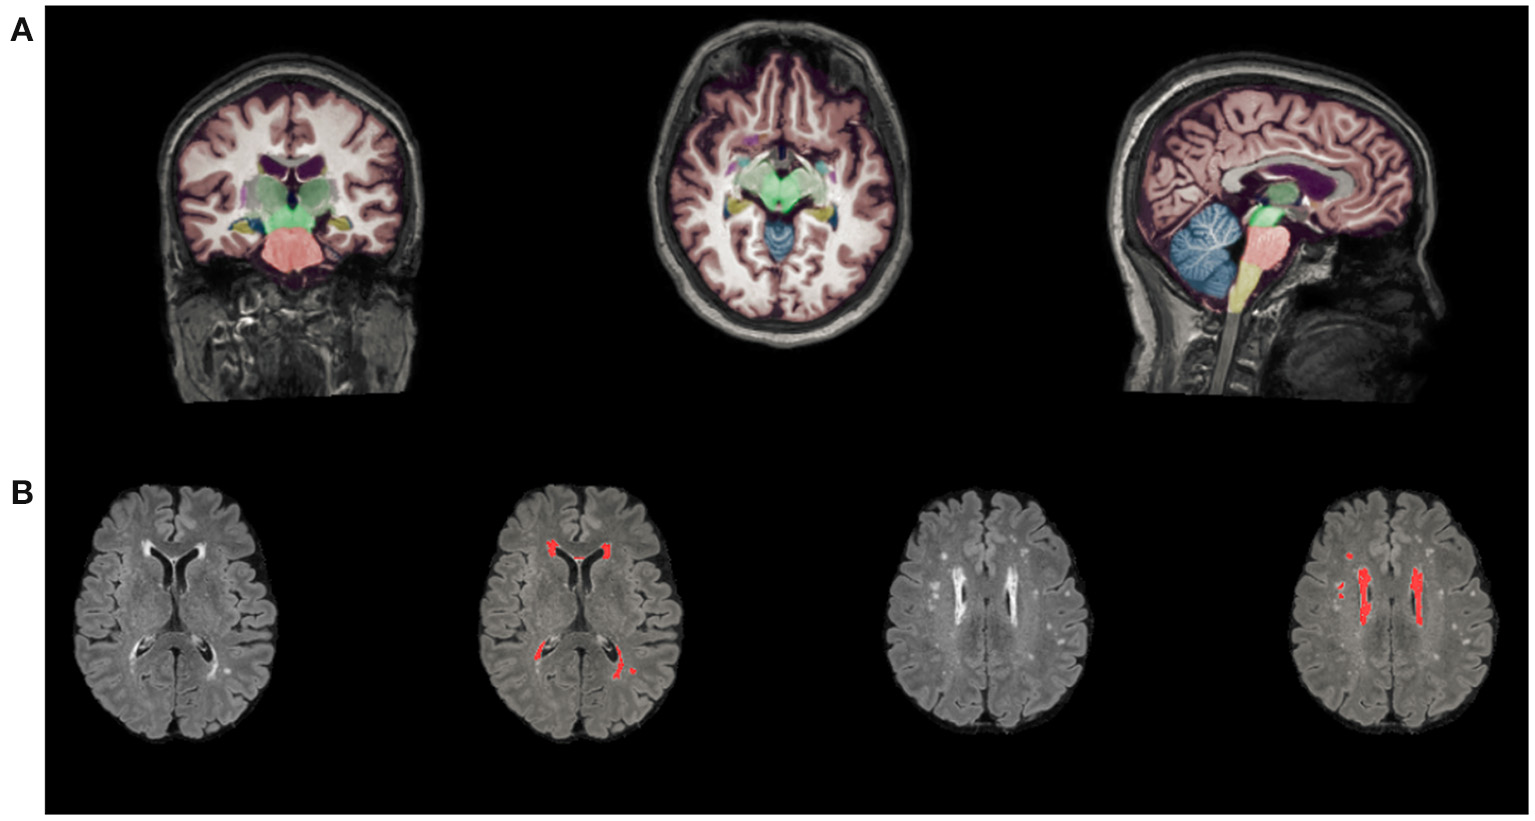

The number of LIs (on T1-weighted and FLAIR images) and CMBs (on susceptibility-weighted imaging) was counted by two expert neurologists separately. Volumetry of anatomical regions was obtained from T1-weighted MRI scans automatically segmented using AccuBrain™. The WMH volume segmentation and quantification were based on additional T2-FLAIR MRI images, which were standardized by dividing the volume of different brain regions and WMH volume by the intracranial volume (ICV) for each participant (brain volume/ICV × 100%) Figure 1. MTA is defined as the ratio of the ipsilateral lateral subventricular horn to hippocampal volume.

Figure 1

Automated segmentation and quantitative using AccuBrainâ„¢. (A) Volume segmentation and quantification of anatomical regions based on T1-weighted MRI scans. (B) WMH volume segmentation and quantification were based on FLAIR images. WMH, white matter hyperintensities.